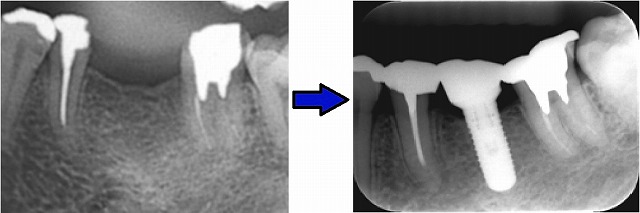

一次審査は、自分がしてきたインプラント治療を20症例提出しなければなりません。しかも治療後3年以上経過している患者様の治療前後のレントゲン写真が必要です。経過が良好でないと、一次審査は合格しませんが、これは無事に合格しました。

私がプレゼンをした治療前後のレントゲン写真ですが、こんな感じです。

見た感じはただ入れただけのように見えますが、実は前歯の重なりを無くすために小矯正をしています。インプラントのスペースを利用して少し狭めてやって、前歯の重なりをなくしています。